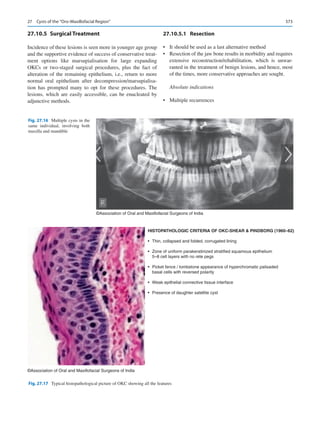

icine man for their healthcare. Direct to consumer marketing